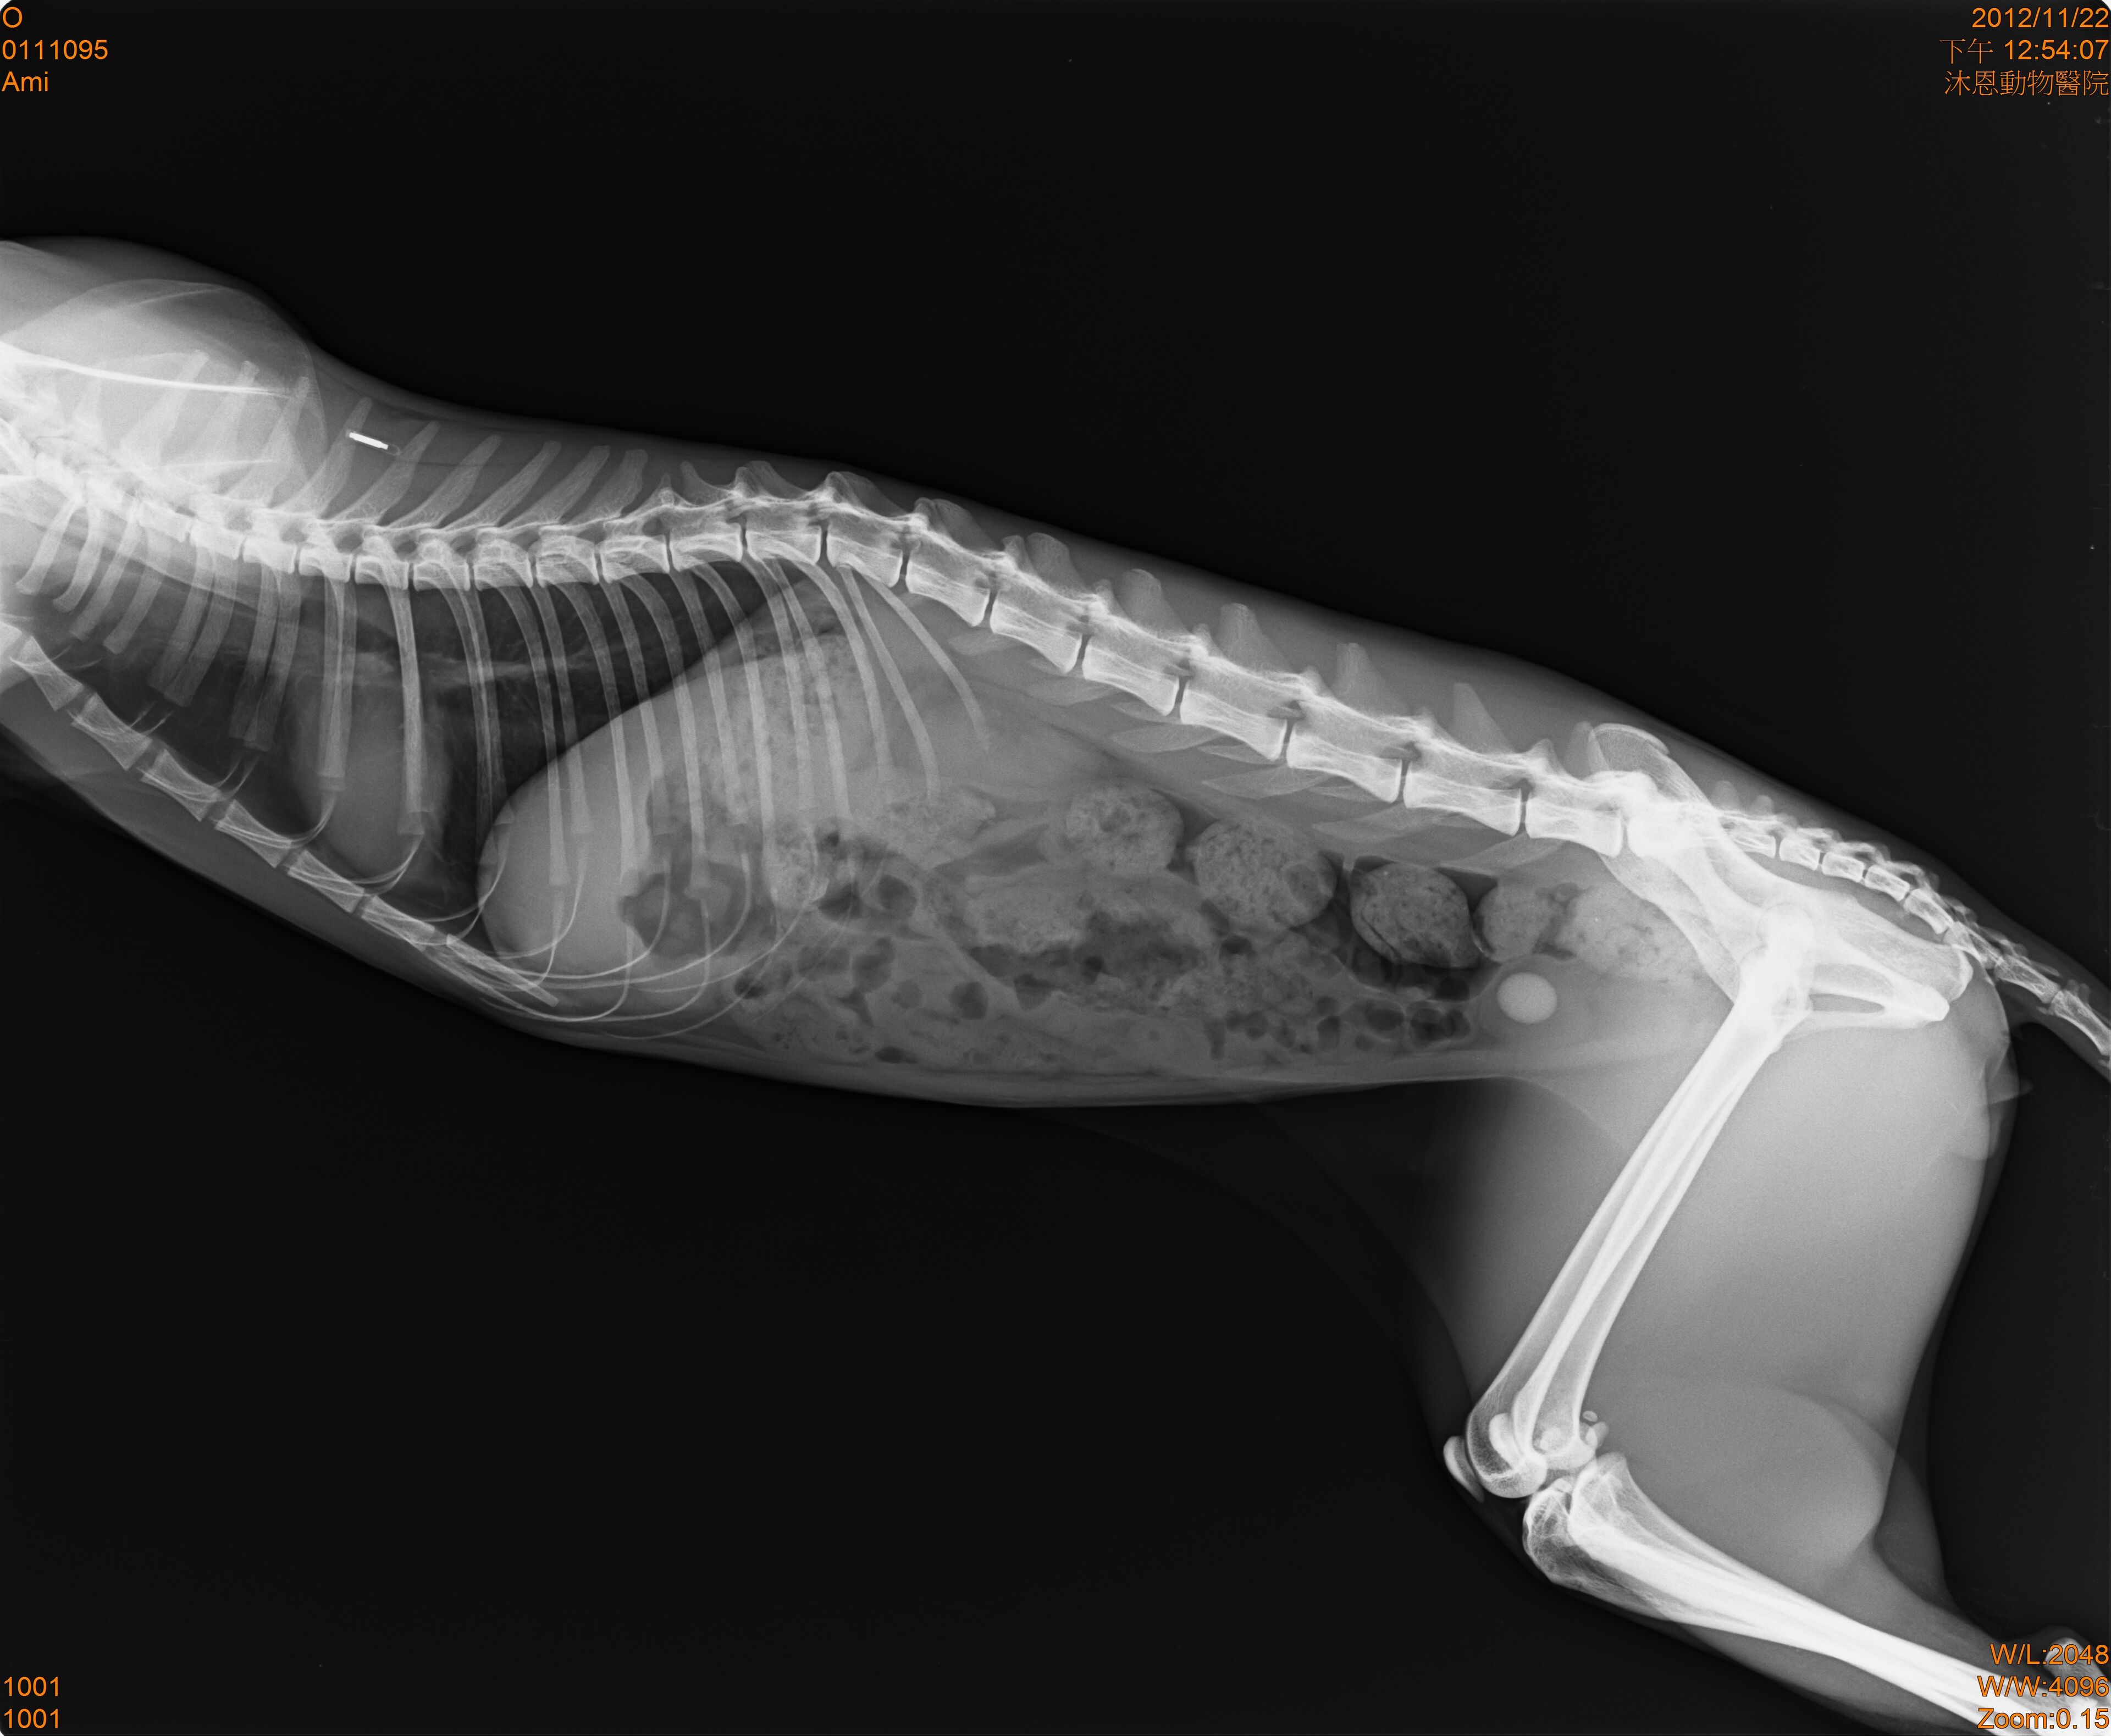

- 編號: 1636

主題: 膀胱結石又有血尿的黑貓 申請者姓名: 鄧伃絜 花色: 申請日期: 2012-12-21 03:00:03 申請者部落格: 申請者臉書網址: https://www.facebook.com/chun.chun.3998?ref=tn_tnmn 所在縣市/合作醫院: 台北市/其他院所醫助專案(醫院請先MAIL溝通) 治療費用: 4225元 需求人數: 10人 已結案 (2013-06-27 14:12:40) 報名人員: 張芳嘉(已付款)、李寧、Summer(已付款)、Hitomi Akanishi(已付款)、芯荷(已付款)、黃咪咪(已付款)、黃先生、李靖汶(已付款)、Ou Han(已付款)、吳毓軒(已付款)、Shirley Tsai x2(已付款)、 候補人員: 動物病情說明: 餵養人是一位法文老師王嫻如小姐

最近突然發現平時照顧的街貓有1隻黑色公貓

他膀胱裡有結石,有血尿

所以要開刀,經費快到一萬塊

原醫療金為9225元-5000元=4225(需要幫忙募的金額)

治療醫院:沐恩動物醫院